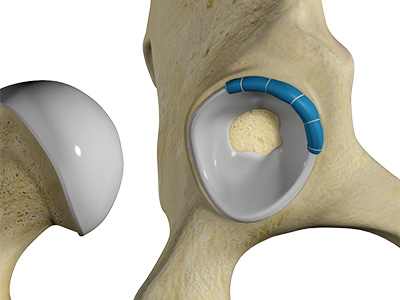

The head of the femur rotates and glides within the acetabulum. A fibrocartilagenous lining called the labrum is attached to the acetabulum and further increases the depth of the socket.

- Acetabular labrum: The labrum is a fibrous cartilage ring which lines the acetabular socket. It deepens the cavity, increasing the stability and strength of the hip joint.

Hip Labral Repair Hip Labral Reconstruction

Hip Labral Reconstruction Hip Preservation Surgery

Complex Hip Reconstruction Surgery Hip Labral Augmentation

Hip Labral Augmentation Nonsurgical Hip Treatments